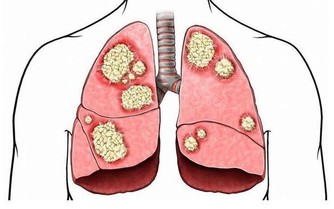

3、心肌缺血

在睡眠的前半段其實主要是大腦皮層的抑製作用,以及身體疲憊和習慣使然的共同結果,睡眠的後半段才是身體真正的休眠。

當心臟供血不足時,會影響到大腦的供血,這時候大腦容易處於一個比較興奮的狀態,來刺激心臟的正常供血。